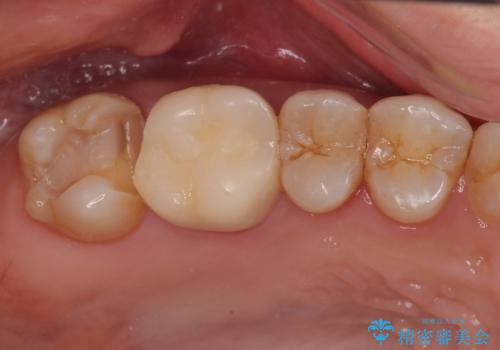

- 当院で矯正終了後に銀歯をやり替えたいとのことで来院された患者様です。

右上の6番目の歯はメタルインレーが大きかったためルジルコニアクラウン、右上の7番目の歯は一番奥で審美的な要素よりも機能面を重視してゴールドインレー修復による治療計画を立案しました。

拡大鏡視野下で保険のプラスチック(コンポジットレジン)、虫歯を除去し、フルジルコニアクラウン、ゴールドインレーに適した形にしました。